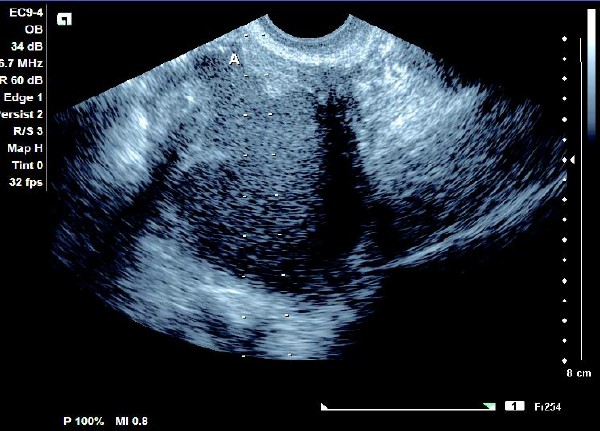

1.单纯囊肿型

(1)单侧或双侧卵巢内呈现椭圆形或圆形无回声暗区,其内充满弱回声光点,囊肿直径一般为5~6 cm,大于10 cm 的较少见。

(2)壁较厚,囊内充满细小均匀点状回声,后方回声增强。

(3)常与周围组织有粘连,边界清晰。

(4)CDFI 探测:囊壁及囊腔内无血流信号。

患者,女,35岁。每次月经量少,痛经,近来行经期延长、疼痛加重来院诊治。超声报告显示子宫前倾位,子宫体大小为:5.9cm×5.1cm×4.8cm,形态规则,边界清晰,宫避回声匀称,宫腔线居中,内膜厚度0.6cm,宫内未见异常回声。右侧卵巢内可见大小约5.2 cm×4.9cm的无回声区暗区,壁厚,内壁欠光滑,内见密集细光点,边界清晰。CDFI探测囊壁及囊腔内无血流信号。

超声提示:右侧卵巢巧克力囊肿